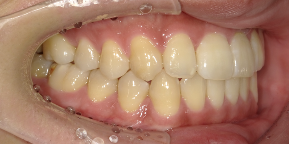

33歳女性のビフォーアフター

| 診断 | 空隙 |

| 治療方針 | 治療方針:前歯の咬合関係改善と空隙閉鎖を主な目的にて主にIPR(歯と歯の間をわずかに削合してスペースを獲得する方法)を組み込んだ動的矯正治療を行い、空隙、前歯咬合を改善後、保定を行う。臼歯部の咬合関係はプランの都合上維持することとした。 |

| 治療費 ※ | 67万8千円(診断、型取り、矯正中のメンテナンス、保定装置を含む料金) |

| 治療期間 | 6か月 |